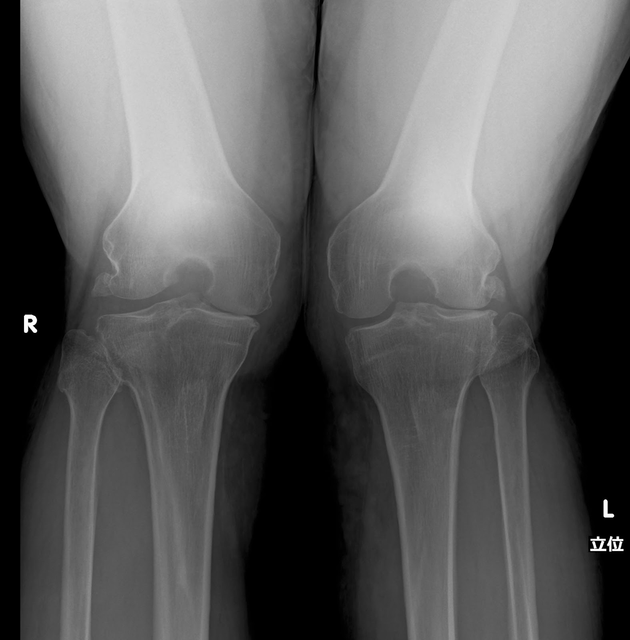

レントゲン・MRI検査

膝関節症の症状を確認するためのMRI検査(外部機関)と足の骨格姿勢を荷重下レントゲンで検査。

変形性膝関節症って?

変形性膝関節症(Osteoarthritis of the knee)は、膝関節の軟骨が徐々に摩耗し、骨同士が擦れ合って変形することで痛みや腫れ、関節の動きの制限などの症状が生じる病気です。これは、関節の機能が低下し、歩行や立ち上がりなどの日常生活動作に影響を与えることがあります。